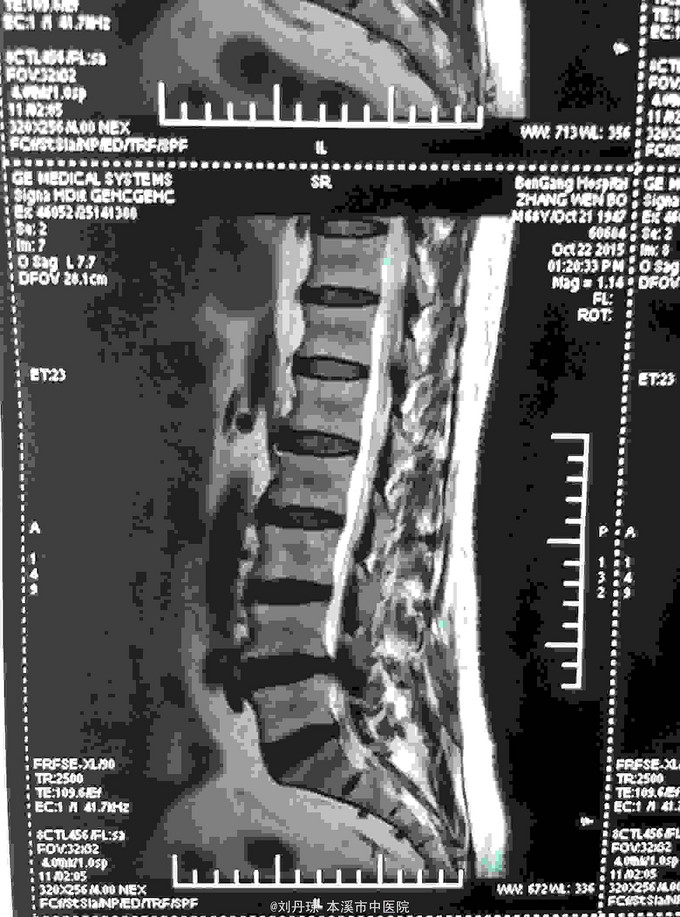

腰部间歇性钝痛伴左下肢放射痛麻木感半年。患者半年前无明显诱因感腰部间歇性钝痛伴左下肢放射痛麻木感,经多家医院治疗未见明显好转,今日来我院门诊求治,门诊医师以“ 腰椎间盘突出症、骶管囊肿 ”收入院治疗。

L4-S1棘突左侧1厘米压痛阳性,直腿抬高试验左40º右60º,加强试验左侧(阳性)右侧(阴性),腰椎功能障碍。左腿前外侧及足背外侧感觉减弱。 辅查CT: 腰椎间盘突出症、骶管囊肿